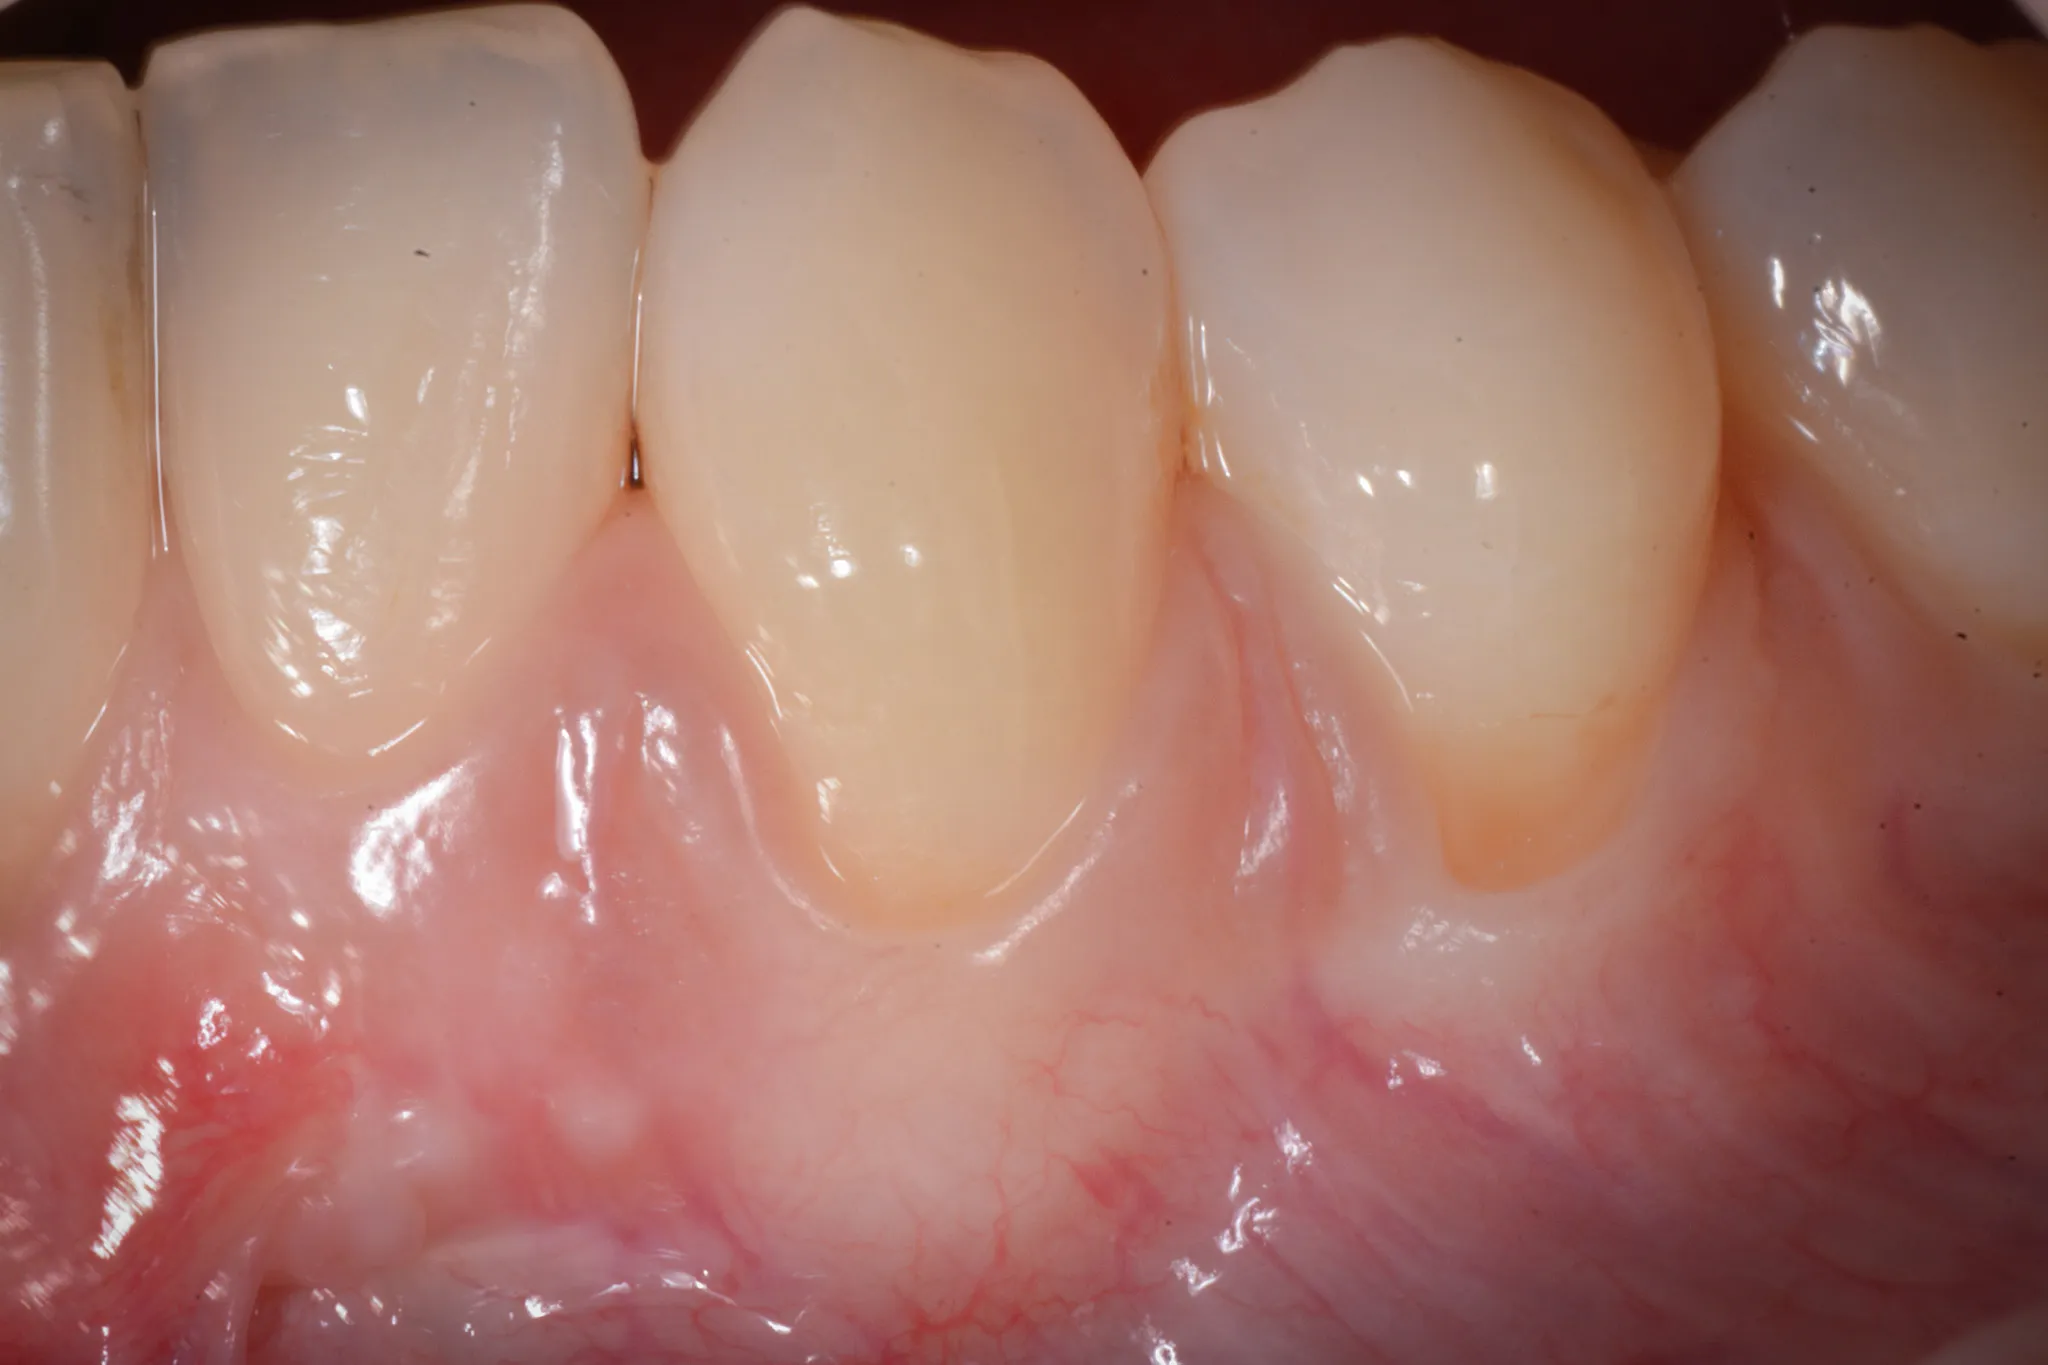

Il tessuto gengivale vero è un tessuto connettivo rivestito da epitelio cheratinizzato (in sostanza, un tessuto più spesso e resistente adeso all’osso sottostante). Quando si ritira, espone la radice del dente — una superficie che non è progettata per stare a contatto con l’ambiente orale. La radice è più porosa dello smalto, più vulnerabile alla carie, più sensibile agli stimoli termici.

Inoltre, a volte la gengiva si assottiglia per vari motivi lasciando spazio da un tessuto più delicato (mucosa orale) che è identico a quello che riveste le guancie e l’interno delle labbra.

Il dente che “sembra più lungo” è il segno visivo. Il paziente lo nota allo specchio, oppure lo nota il dentista durante un controllo.

RT1 — Recessione senza perdita di attacco interprossimale. L’osso tra i denti è integro. È il caso ideale: la copertura radicolare completa è altamente predicibile.